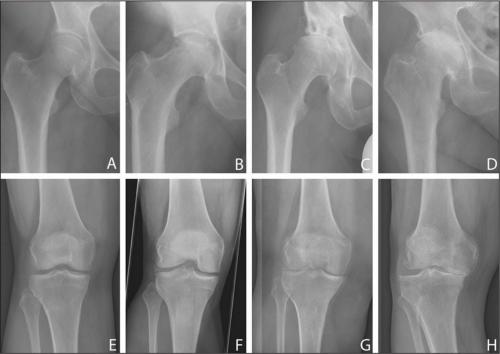

Как восстановить хрящевую ткань тазобедренного сустава. Чем опасно разрушение тазобедренного сустава: признаки и симптомы, тактика лечения

Разрушение тазобедренного сустава сначала происходит бессимптомно, поэтому больной не обращается к врачу. Только спустя несколько месяцев, а иногда и лет возникают первые признаки дегенеративно-дистрофического процесса. Появляются, усиливающиеся, отечность и. На этой стадии деструкции ТБС происходят уже необратимые патологические изменения хрящей, костей, соединительнотканных структур.

Чем раньше больной обращается к ортопеду, тем выше вероятность успешного консервативного лечения с помощью фармакологических препаратов, ежедневных, физиотерапевтических процедур. Пациентам с разрушениями тазобедренного сустава средней и высокой степени тяжести показаны артродез или.

Суставная жидкость при коксартрозе густая, вязкая. Изменение консистенцииприводит к высыханию поверхности гиалинового хряща, потери им гладкости и прочности. Появление на ней трещин становится причиной постоянного травмирования хрящей при движении, их истончения, усугубления патологических изменений в тазобедренном суставе. Затем начинают деформироваться кости, пытаясь «приспособиться» к увеличению на них давления. В результате ухудшается обмен веществ, провоцируя прогрессирование деструкции, а впоследствии — и атрофию мышц ноги.

Основные симптомы разрушения тазобедренного сустава — сначала редкие, а по мере прогрессирования патологии — сильные, постоянные. Они могут иррадиировать, лодыжку,,позвоночника. На приеме у ортопеда пациенты жалуются на скованность движений. Причем на начальной стадии коксартроза ограничение подвижности кратковременное, исчезающее через 1-2 часа. Человек «расхаживается», и в течение дня скованность при движении его не беспокоит. А вот на третьей стадии дегенеративно-дистрофической патологии для ходьбы больной использует трость или костыли. Нередко он не способен передвигаться по комнате без посторонней помощи. Полная или частичная утрата подвижности сопровождается укорочением ноги и атрофией бедренных мышц.